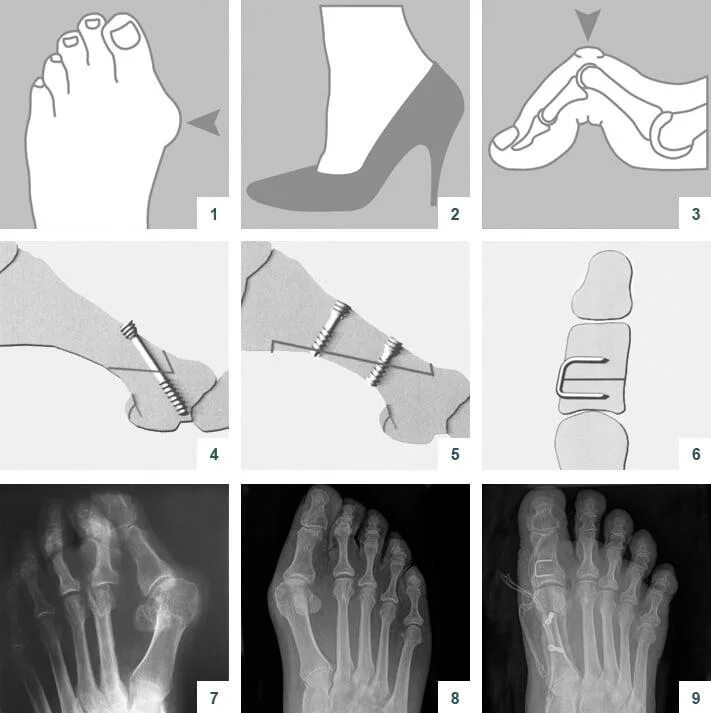

Операция деформации пальцев стопы